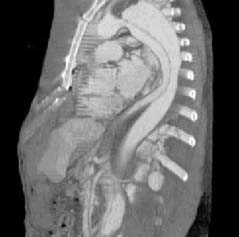

Рис. 4. Сагитальная реконструкция, полученная при сканировании всей грудной клетки на одном вдохе.